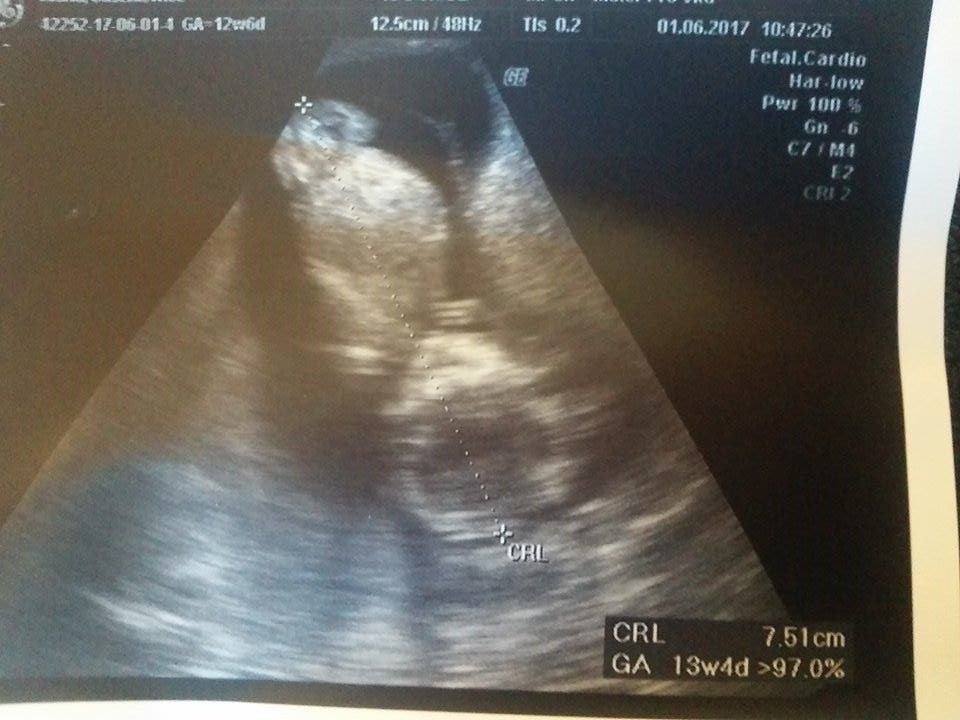

Gratki, kolejny chłopokNo to już jestem... maluszek zamiast 12t6d ma z usg 13t4d / 13t6d zależy od ujęcia do zdjęcia i jak to Pani dr stwierdziła jest ładnym 7.51 cm chłopcem z tętnem 164bpm.

W sumie płeć to było pierwsze co się dało u niego sprawdzić bo całe badanie się wiercił ale tak by prawie non stop mieć nogi rozłożone, aż się lekarka śmiała że wymachuje tym co ma... Nawet na początku powiedziała "nie mogę zbadać przezierności bo tak wysoko jest główka ale płeć widzę, chcecie państwo poznać?" bo miałam pierwotnie dopochwowe ale ze względu na wysokie ułożenie i tak się skończyło ganianiem go przez brzuch.

Ogólnie na ekranie widać go było ładnie tylko ze zdjęciami był problem bo co głowica chwilę w tym samym miejscu była to było widać jak maleństwo sobie ucieka do przodu i do tyłuOstatecznie jak go pani dr nazwała łobuziakiem to się dał pomierzyć w miarę grzecznie

Poniżej przedstawiam Wam małego (z profilu i w całości, gdzie oczywiście też musiał się pochwalić płcią):